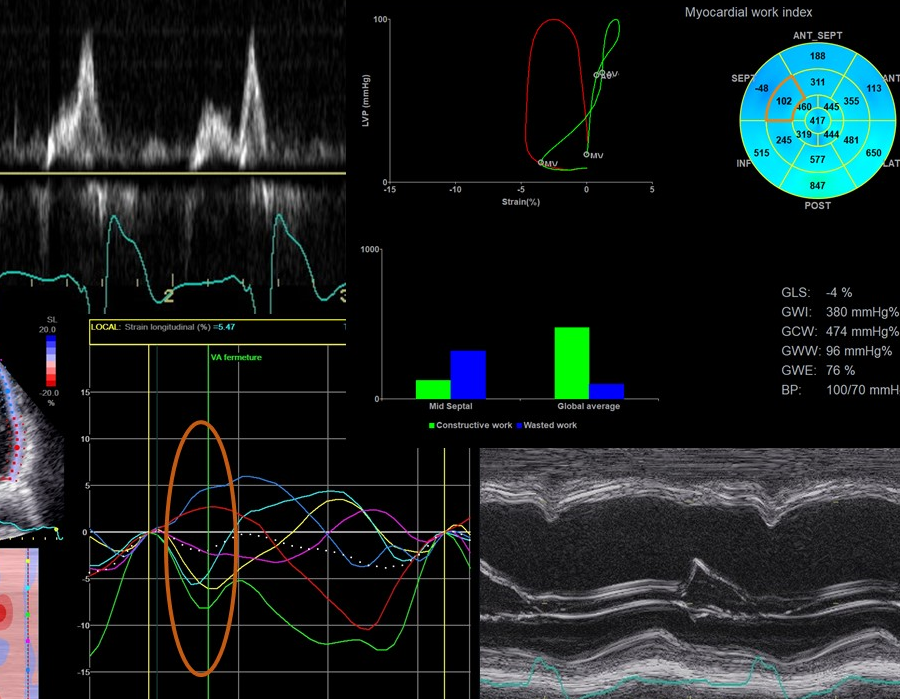

- Imaging in CRT (Erwan Donal)

- Imaging left ventricular dyssynchrony (Otto A. Smiseth)

- Echocardiographic parameters to select patients for CRT (Ivan Stankovic)

- Resynchronization Therapy: How to Assess Ventricular Mechanics? (Jens-Uwe Voigt)